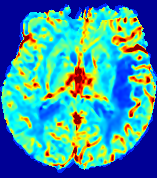

LesionRefer to captionRefer to captionRefer to captionRefer to captionRefer to captionRefer to caption𝐕rgbsubscript𝐕𝑟𝑔𝑏{\bf{V}}_{rgb}Refer to captionRefer to captionRefer to captionRefer to captionRefer to captionRefer to caption𝐕2subscriptnorm𝐕2{\|\bf{V}}\|_{2}Refer to captionRefer to captionRefer to captionRefer to captionRefer to captionRefer to captionRefer to caption3.53.53.52.82.82.82.12.12.11.41.41.40.70.70.70.00.00.0(mm/s)𝑚𝑚𝑠(mm/s)D𝐷DRefer to captionRefer to captionRefer to captionRefer to captionRefer to captionRefer to captionRefer to caption0.0200.0200.0200.0160.0160.0160.0120.0120.0120.0080.0080.0080.0040.0040.0040.0000.0000.000(mm2/s)𝑚superscript𝑚2𝑠(mm^{2}/s)Slice #1Slice #2Slice #3Slice #4Slice #5Slice #6

Figure 4: PIANO feature maps for another patient in the ISLES 2017 training set, where the lesion is located in the right hemisphere. Top row: segmented stroke lesion region (white) on different slices. The corresponding slices for the PIANO feature maps are shown in the following rows.

For a better insight into an estimated velocity field 𝐕𝐕{\bf{V}} and diffusion field 𝐃𝐃{\bf{D}}, we compute the following maps: (1) 𝐕rgbsubscript𝐕𝑟𝑔𝑏{\bf{V}}_{rgb}: Color-coded orientation map of 𝐕=(Vx,Vy,Vz)T𝐕superscriptsuperscript𝑉𝑥superscript𝑉𝑦superscript𝑉𝑧𝑇{\bf{V}}=(V^{x},V^{y},V^{z})^{T}, obtained by normalizing 𝐕𝐕{\bf{V}} to unit length and mapping its 3 components to red, green, blue respectively; (2) 𝐕2subscriptnorm𝐕2\|{\bf{V}}\|_{2}: 222 norm of 𝐕𝐕{\bf{V}}; (3) D𝐷D: scalar field in Eq. 5.

Fig. 3 and Fig. 4 show the PIANO feature maps estimated from two ISLES 2017 patients: all are highly consistent with the lesion in both cases. Details of the blood flow trajectories are revealed in 𝐕rgbsubscript𝐕𝑟𝑔𝑏{\bf{V}}_{rgb} by the ridged patterns and the sharp changes of colors in the unaffected (right) hemisphere, while the flat patterns appearing within the lesion provide little directional information about the velocity and indicate low velocity magnitudes. Velocity magnitudes are more directly visualized via 𝐕2subscriptnorm𝐕2\|{\bf{V}}\|_{2}, from which one can easily locate the lesion where 𝐕2subscriptnorm𝐕2\|{\bf{V}}\|_{2} is low. D𝐷D also indicates lower diffusion values in the lesion, though with less contrast potentially due to the fact that it captures the accumulated effect of CA diffusion at the voxel-level.